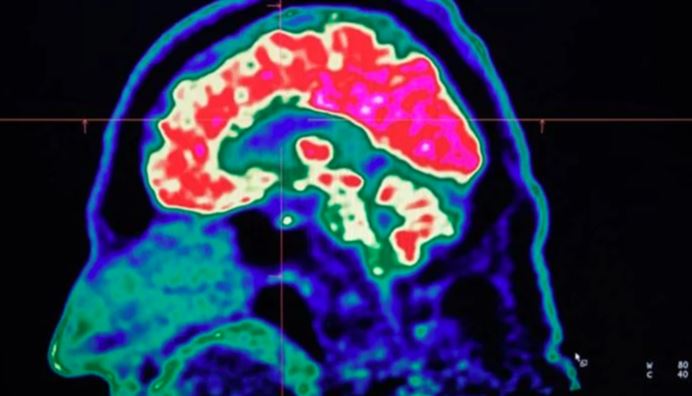

برطانیہ (مانیٹرنگ ڈیسک) انسانی دماغ کی خیالات کا تجزیہ کرنے کی رفتار کی حد کا تعین کا کرنے کے حوالے سے سائنسدانوں نے بڑا کارنامہ کر ڈالا جس کے بعد بڑی کامیابی ملی ہے۔

انٹرنیشنل میڈیا کے مطابق انسانی جسم کا سنسری سسٹم بشمول آنکھیں، کان، جِلد اور ناک ہمارے اردگرد کے ماحول سے اوسطا ایک ارب bits فی سیکنڈ کے رفتار سے ڈیٹا اکٹھا کرتے ہیں مگر محققین نے دریافت کیا کہ ہمارا دماغ ان سگنلز کا تجزیہ محض 10 bits فی سیکنڈ کی رفتار سے کرتا ہے جو کہ ڈیٹا موصول ہونے کے مقابلے میں کروڑوں گنا کم ہے۔ اس کے مقابلے میں ایک روایتی وائی فائی کنکشن فی سیکنڈ 5 کروڑ bits ڈیٹا کا تجزیہ کرتا ہے۔ دماغ میں 85 ارب سے زائد نیورونز موجود ہیں جن میں سے ایک تہائی اعلی سطح کے خیالات سے جڑے ہوتے ہیں۔

محققین نے بتایا کہ ہر لمحے میں ہم اپنے اردگرد سے موصول ہونے والے اربوں کھربوں bits کے ڈیٹا میں سے محض 10 bits کا تجزیہ کرتے ہوئے فیصلے کرتے ہیں۔ محققین نے انسانی رویوں جیسے مطالعے، لکھنے، ویڈیو گیمز کھیلنے اور دیگر پر ماضی میں ہونے والے تحقیقی کام کا تجزیہ کیا اور تخمینہ لگایا کہ انسانی خیالات کی رفتار محض 10 bits فی سیکنڈ ہے۔ انہوں نے مزید بتایا کہ اس سے یہ سوال پیدا ہوتا ہے کہ ہمارا دماغ باقی ساری تفصیلات کو کس طرح فلٹر کرتا ہے۔